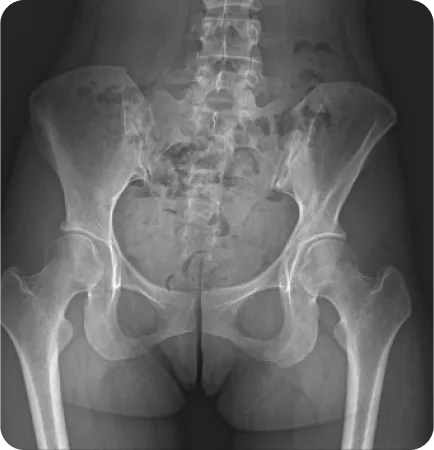

성인의 80%~90%에서 골반 부정렬이 발견되었으며,

그 중 3분의 1은 무증상, 3분의 2는 요통, 골반통 등의 증상을 호소한다.

Wolf Schamberger - The Malalignment Syndrome 中

골반 틀어짐 유형별 치료

유형 이미지 특징 치료법

틀어진 골반

(업슬립)

짝궁둥이 체형, 종아리에 비해

허벅지가 두껍고 골반높이 차이가

심한 경우

• 실제 다리길이 차이가 있는지 확인

• 맞춤깔창 처방

• 정골추나요법, 골반 도수 동시 시행

• 중둔근 강화 및 대퇴근막장근 이완기법